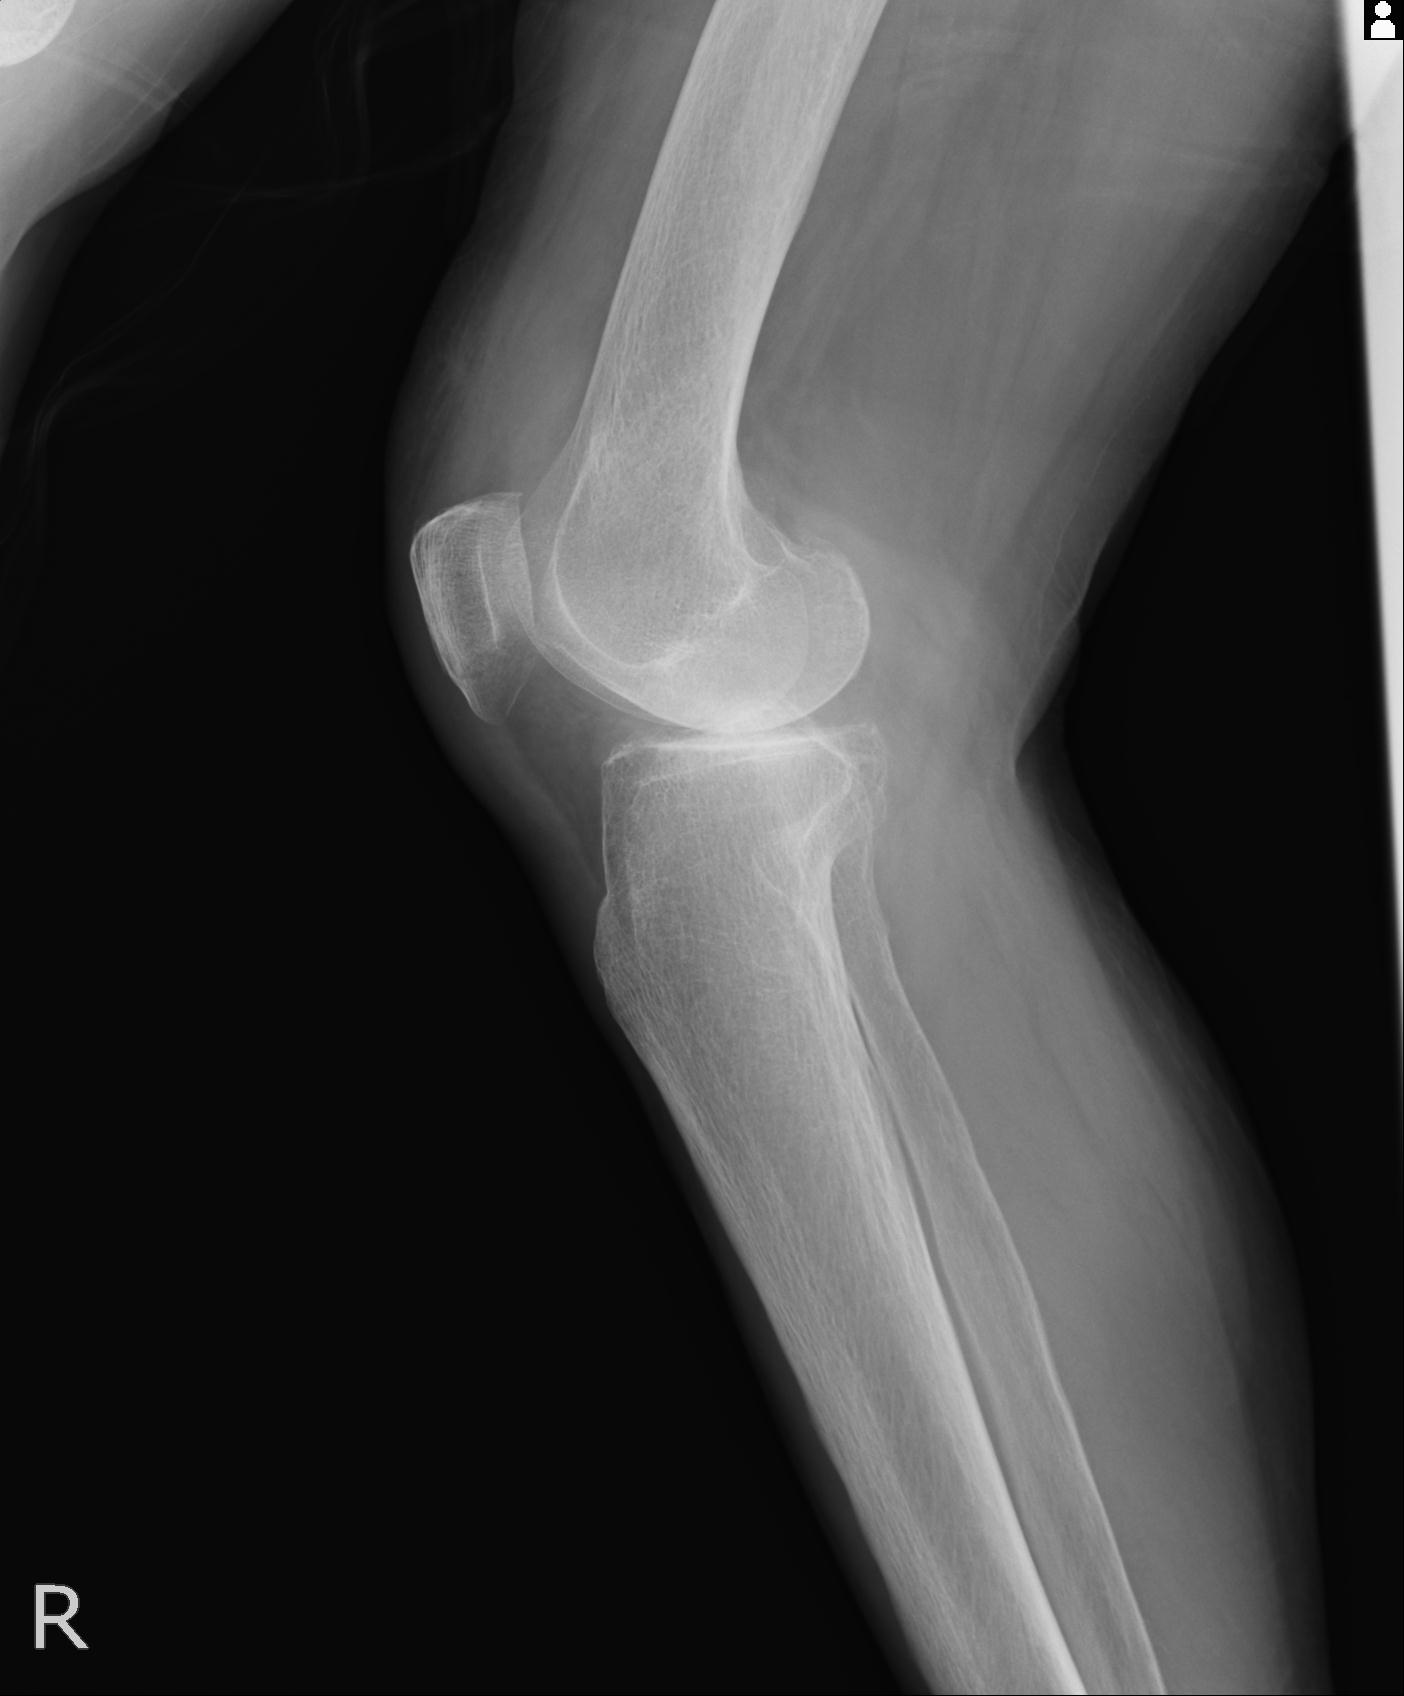

49554 3/13 膝 4R 3/16 4R 1/18 2R 78歳男性 膝蓋骨骨折